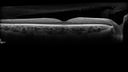

White Retinal Artiole Left eye - Inferotemporal430 views31 year old female with migraines and headaches for the last 12-13 years. Sometimes she gets the visual symptoms with the migraine. When she gets the migraines the pain is on the left side of her head. She gets the problem a few times a month, sometimes more. They usually last 5-6 hours. She has not had a permanent vision change. When she gets a vision change there are spotty dots of blue neon lights in her vision. With her glasses her two eyes are about the same. VA 20/16 in Each Eye     (0 votes)